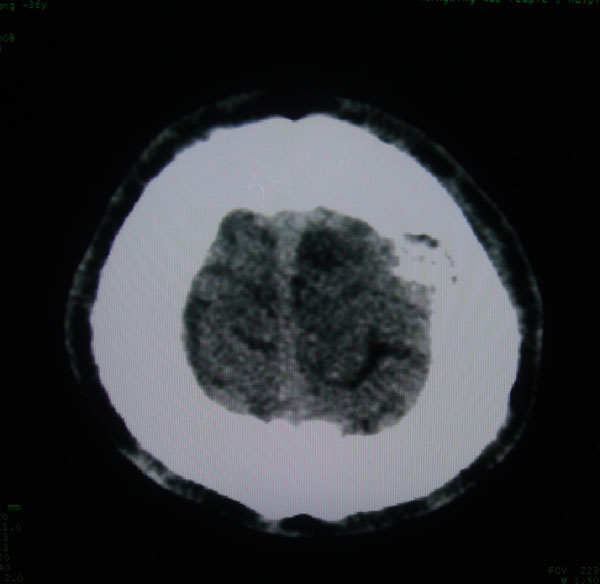

以下是引用zhangzhongshou在2008-6-7 12:49:00的发言:[br]左顶骨嗜酸性肉芽肿可能性大,建议ect及其他检查,除外转移瘤的可能。

以下是引用拾荒者在2008-6-7 13:05:00的发言:[br]左侧顶骨局限性骨质缺损,边缘锐利,无硬化边,周围软组织轻度肿胀,无明显软组织肿块及骨膜反应,考虑嗜酸性肉芽肿可能。